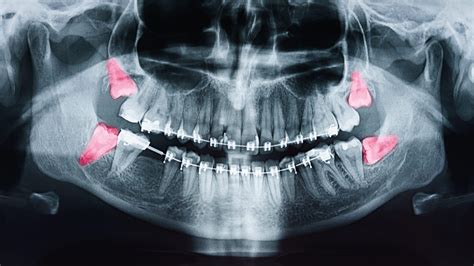

Impacted wisdom teeth can grow at various angles: toward the adjacent molar, toward the back of the mouth, or staying trapped completely within the jawbone. Below is a breakdown of how different types of impaction affect your oral health:

Impaction Type Description Risk Factor

Soft Tissue Impaction The tooth has broken through the gum but not fully. High risk of infection (pericoronitis).

Partial Bony Impaction The tooth is partially encased in the jawbone. Difficult to clean; high risk of cavities.

Full Bony Impaction The tooth is entirely enclosed in the jawbone. Potential for cysts or damage to adjacent teeth.

There comes a point where home remedies are no longer enough. Your dentist will monitor the progression of your wisdom teeth coming in through routine dental X-rays. These images provide a clear view of how the teeth are oriented and whether they are likely to cause future damage to your healthy second molars. You should make an appointment if you experience:

Navigating the phase of wisdom teeth coming in is a common experience that requires patience and vigilance. By monitoring your symptoms, maintaining excellent oral hygiene, and staying in regular contact with your dental care provider, you can manage this transition safely. While the prospect of a potential extraction might seem daunting, modern dentistry has made the procedure routine and highly manageable. Prioritizing your oral health today prevents long-term complications, ensuring that your smile remains healthy, aligned, and pain-free well into the future. Always rely on professional X-rays and dental assessments to guide your decisions, as every individual’s jaw structure and tooth development are unique.